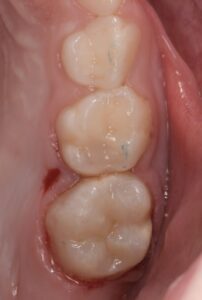

Le congrès de l’EAPD (Académie Européenne d’Odontologie Pédiatrique) a défini des critères de diagnostic en 2003. A savoir des opacités délimités, des fractures post-éruptives, des restaurations atypiques ainsi que que des extractions des molaires. (3) Le diagnostic différentiel doit surtout s’établir entre des amélogénèses imparfaites et des hypominéralisations d’origine traumatique pour les dents antérieures. Cliniquement, les dents vont présenter des colorations blanches ou brunes opaques sur une partie ou sur toute la surface de la dent (Figures 1-2-3-4).

Cette atteinte peut être soit légère (émail blanc, opaque), soit modérée (coloration jaune, brune, surface crayeuse et effondrement postéruptif de l’email ou PEB) ou enfin sévère (atteintes associées à des pertes de substances importantes). De plus, l’intégrité de la dent peut être aussi touchée. Plus la MIH est sévère et plus le manque d’émail sera important donc plus les sensibilités/douleurs seront importantes aussi. Cette sévérité varie en fonction des personnes, mais également au sein des dents d’un même individu : on parle d’atteinte asymétrique. Toutes les dents ne sont pas toutes touchées de la même façon, et ne nécessiteront donc, pas les mêmes types de soin.

Pour les secteurs postérieurs, en fonction du délabrement tissulaire (PEB ou consécutif à une atteinte carieuse), on optera pour des restaurations directes en composite (Figures 11-12).

ou indirectes de type onlay en céramique (Figures 13-14-15).

Figure 3-4 : Molaires atteintes de MIH (HSPM + MIH pour la figure 3)

Figures 13-14-15 : TraitemEnt postérieur par onlay céramique.